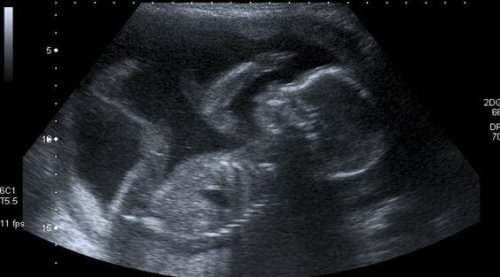

Une femme se sait mère quand, à sa première échographie, elle ne peut retenir ses larmes d’émotion en écoutant le cœur de son enfant battre rapidement, tout comme le sien quand elle déborde de joie à ce premier contact.

Cependant, cette maman sait que pour le moment et pour au moins neuf mois, elle devra se contenter des images que les rayons X montrent afin de mettre un visage sur son fils, en ressentant ces mouvements subtils du bébé, qui deviendront plus actifs.